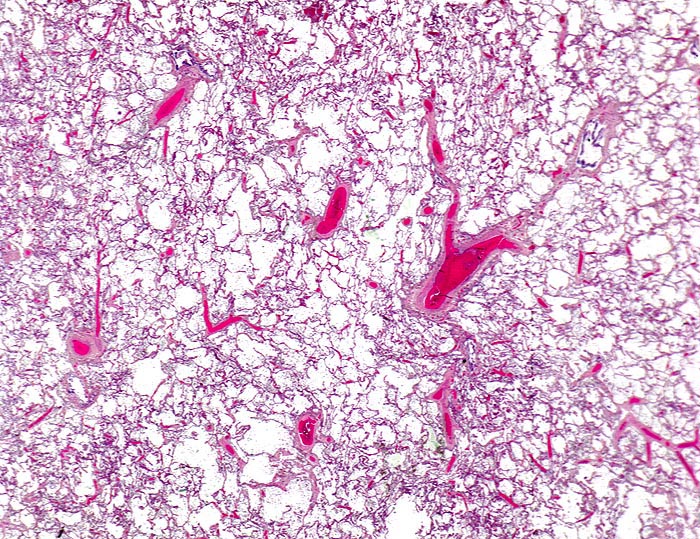

chronische Lungenstauung: Venulosklerose

Starke Blutfülle der Alveolarsepten. Die angeschnittenen Venen zeigen eine deutliche Wandverdickung.

Patient mit koronarer Herzkrankheit und Linksherzinsuffizienz.

Venen sind im Lungenparenchym daran erkennbar, dass sie im Gegensatz zu den Arterien nicht in unmittelbarer Nachbarschaft eines Bronchus liegen. Die Wanddicke einer normalen Pulmonalvene beträgt maximal 5% des Gefässdurchmessers.